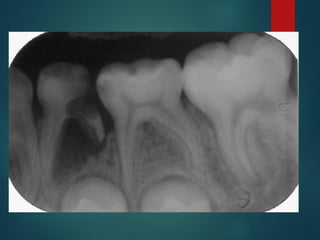

La caries es detectable

radiográficamente por que

produce una desmineralización del

diente, esta zona permite un paso

mayor de Rayos X que impresionan

la película

“ La extensión histológica de

una caries no corresponde con

el límite radiográfico, siempre es

mayor ”